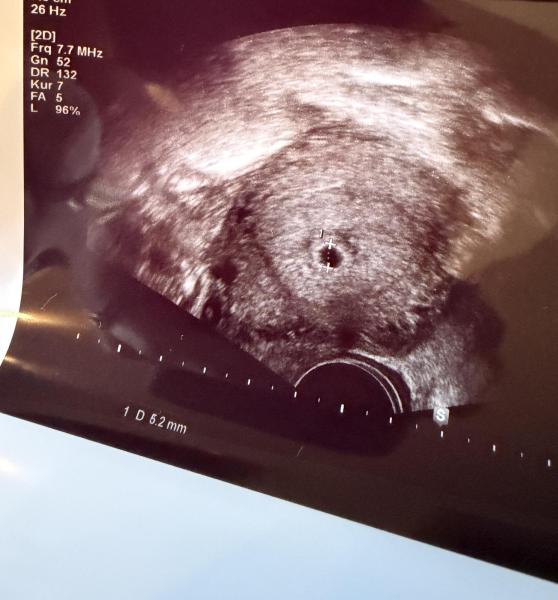

Hallo, wir hatten heute unseren 1. Termin. ich habe mir mehr erhofft als das was ich gesehen habe. am 12.10 habe ich positiv getestet, mein hcg Wert am 15.10 lag bei 80. Am 21.10 Stand clearblue 2-3. Mein Ovu war positiv am 29.9/30.9 Heute dann Ultraschall und das Foto kam bei raus. Was schätzt ihr wo ich bin? Ich dachte eig man sieht schon oder muss schon einseitig den Dottersack sehen. Ich bin über jede Hilfe dankbar von euch..

Gehen wir von ES am 1.10. Aus (Ovus sind ja keine Garantie für ES), dann wärst du jetzt anfangs 6.ssw. da muss man noch keinen Dottersack sehen ;-) Du bist schwanger, herzlichen Glückwunsch. Der Rest wird sich in den nächsten Wochen zeigen.

Entscheidend ist ja der erste Tag der letzten richtigen Regelblutung. Ovu-Tests können nicht sagen, wann der Eisprung genau war oder wann die Einnistung war. Deshalb legt man ja immer diese rechnerische Standardgröße letzter Mens-Termin zugrunde, damit man einen Fixpunkt hat. Ich denke, du bist Ende der 5. oder Anfang der 6. SSW. Und zu diesem Zeitpunkt muss man noch nichts im Ultraschall sehen. Der Embryo plus Herzschlag muss in der 7. SSW auftauchen (ab 6+1), so steht's im Lehrbuch und so stimmt es auch in den allermeisten Fällen. Bis dahin hilft leider nur warten, das Problem haben ja alle in der Früh-SS. Es ist nicht leicht, ich weiß, ging mir auch immer so. Die Ungewissheit der ersten Zeit nervt, aber da muss man durch. Ich würde aber mal davon ausgehen, dass alles gut ist bei dir. LG und eine schöne Kugelzeit